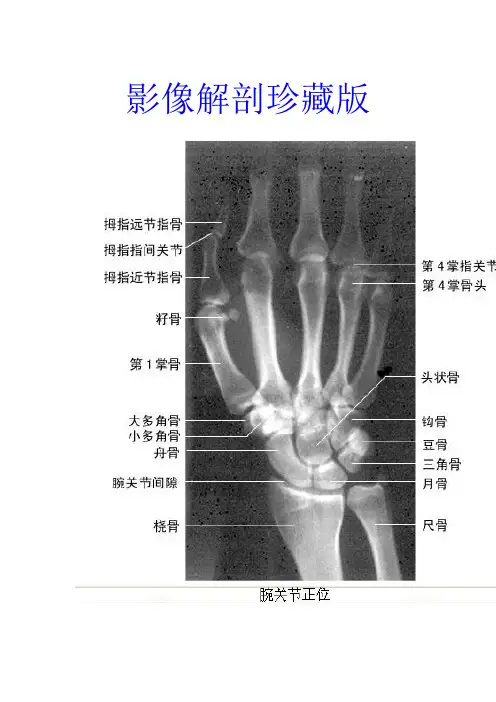

全网最全全身大关节影像解剖,不容错过(更新版)

骨关节影像诊断一直是我们临床工作中的难点,其解剖复杂,肌肉、肌腱多,部分关节损伤诊断困难,为提高各位对关节正常解剖的认识,特总结一下栏目。

腕关节MRI(点击下图)

高清腕关节断层解剖图谱(点击下图)